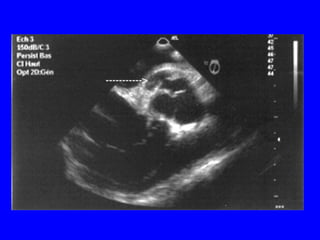

Echocardiogramme dans la RAo

• Confirme un diagnostic clinique:

épaississement ou calcification des valves

dont l’ouverture est diminuée.

• Apprécie le degré: gradient et surface

(équation de continuité ou planimétrie en

ETO).

• Donne des renseignements étiologiques.

• Apprécie le retentissement VG ( hypertrophie,

fonction systolique et diastolique).

• Recherche une valvulopathie associée et ou

une pathologie de l’aorte ascendante.

Echo du RAo

Vitesse du jet